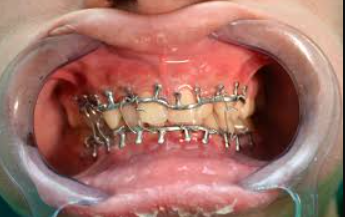

Fractured jaws may require open reduction surgery, jaw wiring for immobilization, and dental crowns and braces to restore a normal bite. Lacerations may need suturing.